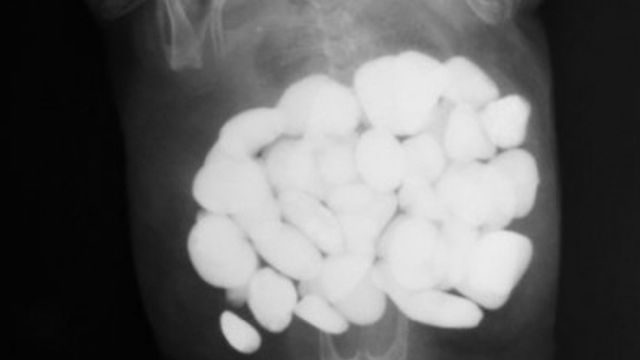

Kermit la rana ha una passione per il collezionismo: ha mangiato più di 30 pietre ornamentali. Il cane da punta Marley ha ingoiato un intero spiedo da Kebab, mentre il suo collega danese Lucky ha inghiottito 43 calze e mezzo. Sono i primi tre piazzamenti del concorso "They ate What?" che premia le più impressionanti fotografie ai raggi X delle interiora di animali affamati e i loro incredibili spuntini.

Tutti gli animali fotografati stanno bene e gli stranissimi oggetti contenuti nei loro stomaci sono stati rimossi in cliniche veterinarie. L'assicuratore per animali Tripanion ha sponsorizzato il concorso e concesso un premio di 3.000 dollari alle radiografie vincitrici. Il denaro è servito a pagare le cure rese necessarie dalle strane voglie di questi famelici cuccioli.